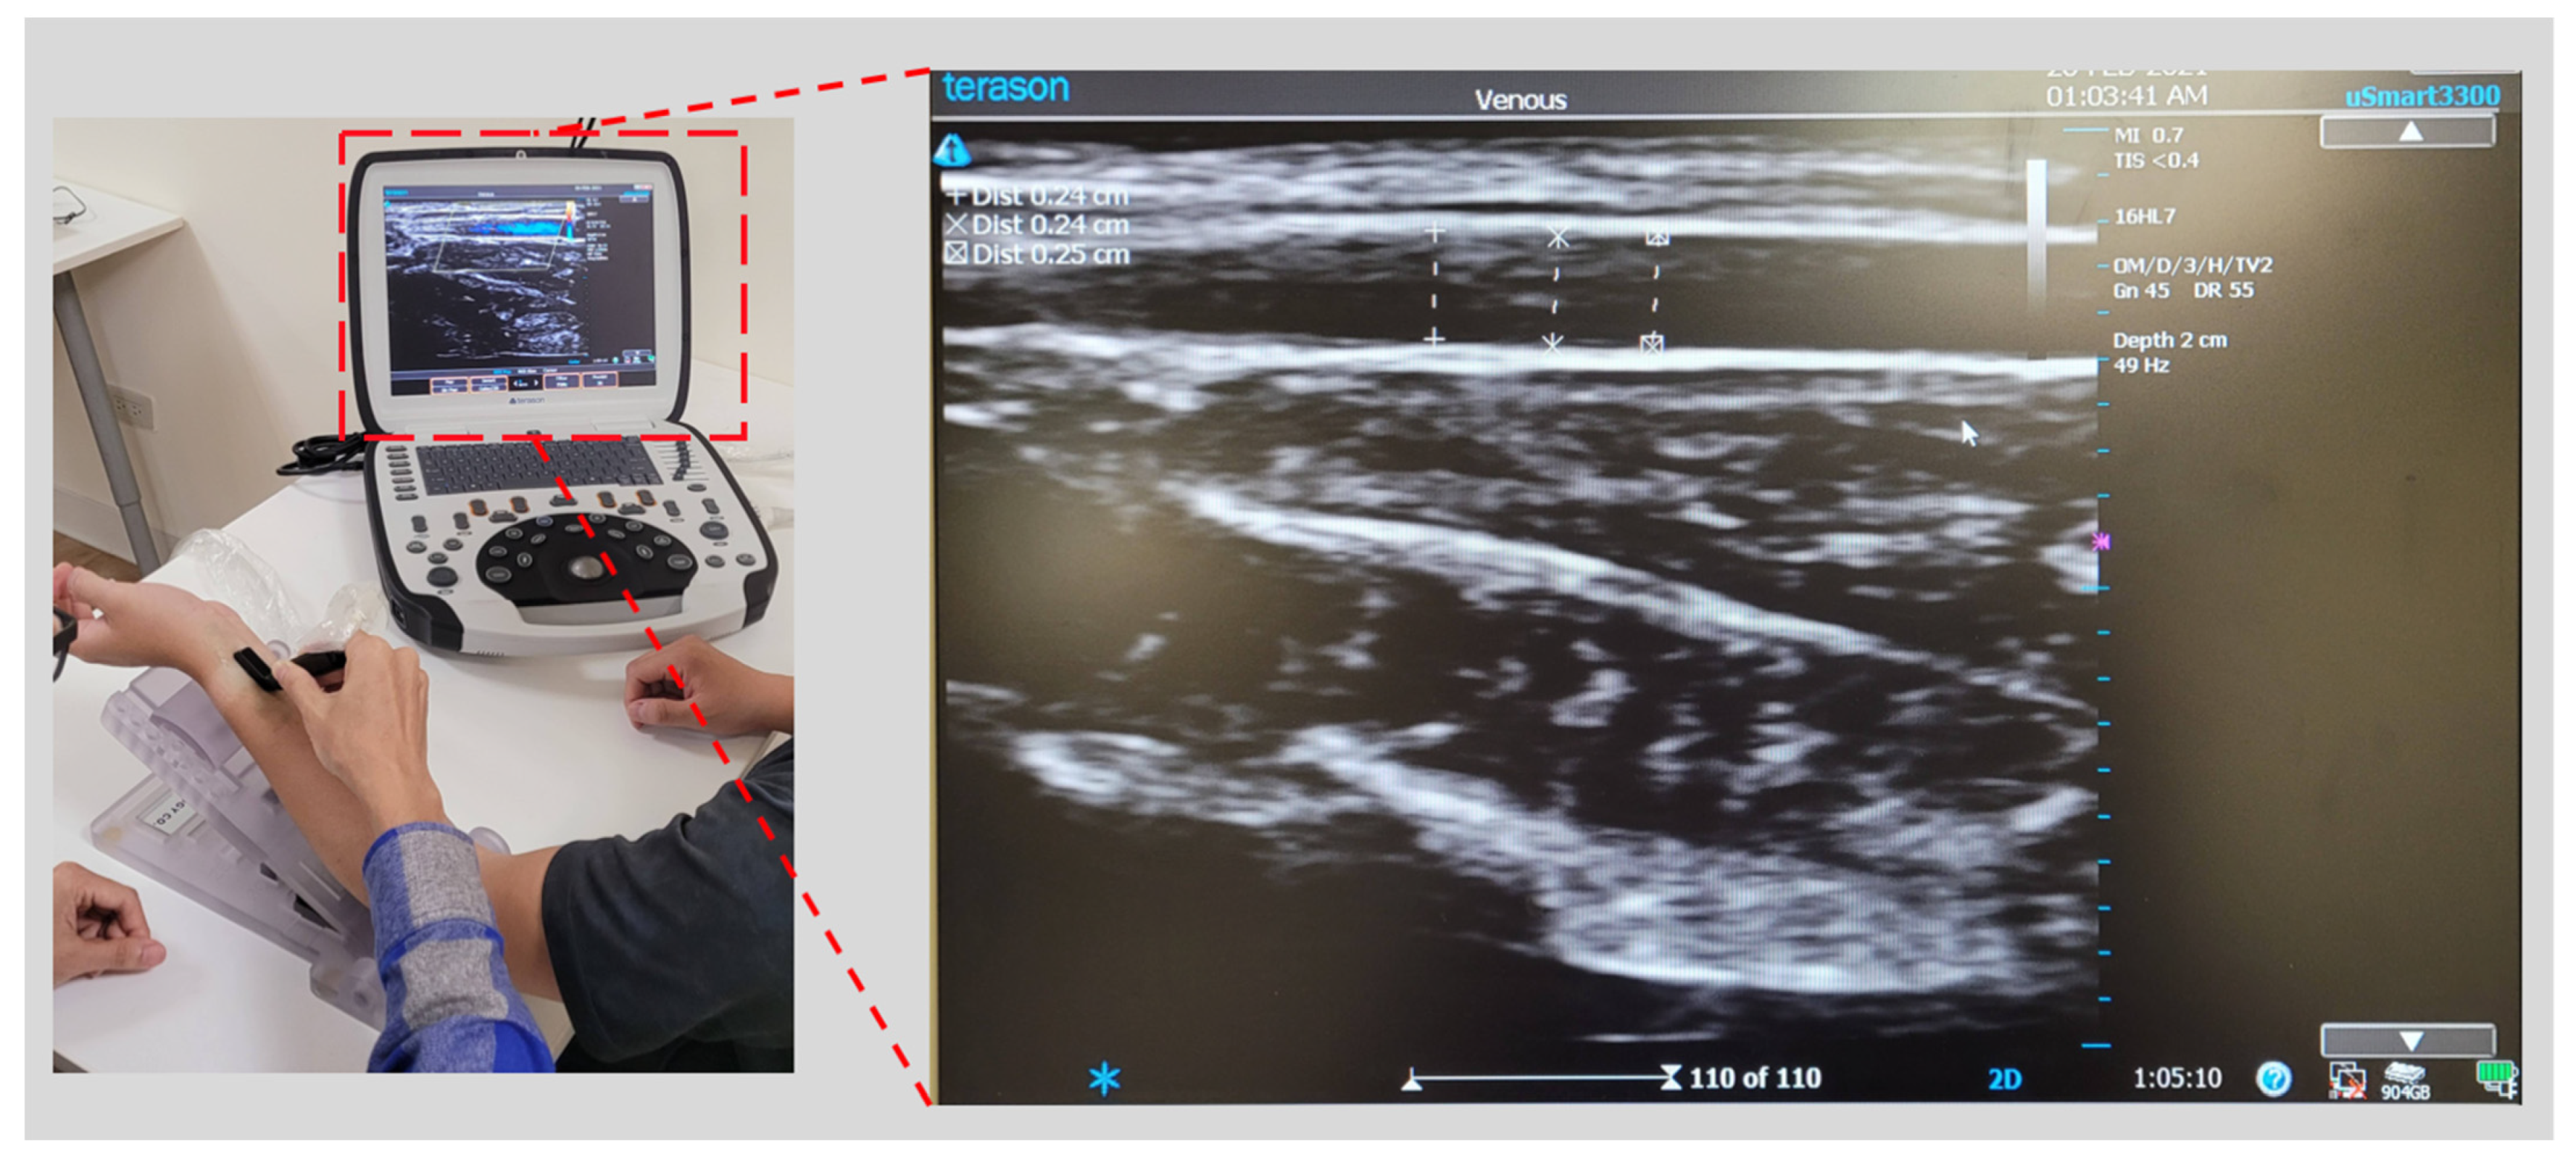

To improve the accuracy of the BP estimation model in this study, it was necessary to measure the patient’s arterial compliance. We used the PPG sensor to quantify the patient’s arterial dimensions and arterial change. The PPG sensor we used is a diffuse reflectance spectroscopy (DRS) sensor that integrates three wavelengths of light-emitting diode (LED) and a photodiode (PD) [36] to ensure that the PPG sensor is placed on the skin surface parallel to the radial artery. When the piezoelectric sensor array of the cuffless BP monitor detects the pulse wave, it will determine that the SNR of the pulse wave qualified the set threshold, indicating that the device is placed on the artery. At this point, the PPG sensor is activated to sense the optical signal of arterial change. When the photons excited by the PPG sensor enter from the epidermal tissue and return to the PD, the optical information of the tissue can be obtained [37]. The depth of the photons entering the tissue depends on the distance of LED to PD and wavelength. To measure the optical characteristics of the tissue as deeply as possible, we chose infrared light with a wavelength of 880 nm as the PPG signal for our estimation of arterial changes. The ADC sampling rate is 100 Hz and the resolution is 18 bits, because infrared light can enter the tissue more than visible light. The deeper the depth, the more tissue optical information can be obtained [38,39]. The distance between the LED and PD is 3 mm. Since the light path of the photon in human tissue is banana-shaped [40], the detection depth can be greater than 3 mm, which affects the radial artery depth. The main factor is the body mass index (BMI) [41]. In most cases, the radial artery depth is approximately 2.5 mm in individuals with a BMI of less than 30 [42,43]. After determining that the PPG sensor has known physical parameters and the radial artery’s physiological characteristics, we used an ultrasonic imaging device as a reference instrument to model the arterial parameters measured by ultrasonic imaging and the quantized PPG signal [44]. The instruments we used included an ultrasonic imaging device (a uSmart 3300, produced by Terason, Burlington, MA, USA) and an L-type probe (a 16HL7, produced by Terason Inc., Burlington, MA, USA) to sample the radial artery parameters of the participants. The researcher operated the L-type ultrasound probe to collect an ultrasound image of the participant’s radial artery and measured the depth, diameter, change, wall thickness, and other information (see Figure 7).

Figure 7. Ultrasound image acquisition of radial artery.